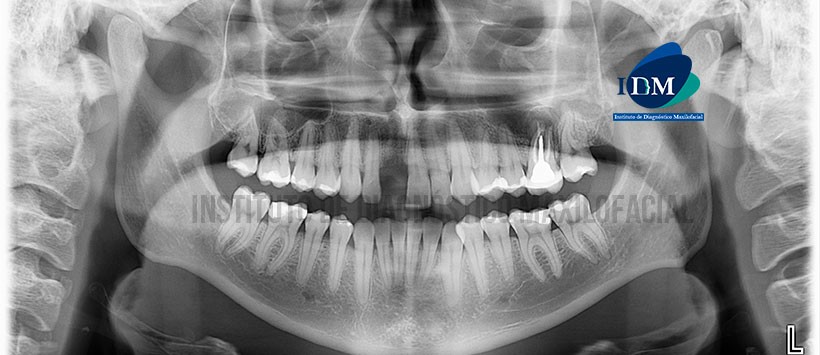

A la evaluación de la radiografía panorámica (Figura 1) se aprecia facetamiento bilateral de los contornos condilares, opacificación del seno maxilar izquierdo aparentemente asociado a proceso osteolítico periapical de la pieza 26, además se observa engrosamiento de la mucosa sinusal en el lado derecho.